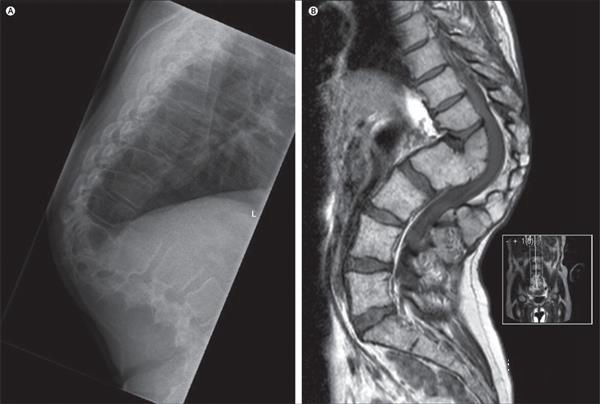

那么,醫(yī)生們是如何完成3D打印鈦?zhàn)倒堑哪?他們首先獲得了受損脊柱的CT和MRI掃描,然后再用3D設(shè)計(jì)軟件將這些掃描轉(zhuǎn)換成可打印的鈦?zhàn)倒悄P停⒂靡慌_(tái)金屬3D打印機(jī)將其打印出來。打印完成后,他們還對(duì)3D打印植入物進(jìn)行了進(jìn)一步的測試,并向印度、瑞典和美國的設(shè)計(jì)團(tuán)隊(duì)尋求幫助。